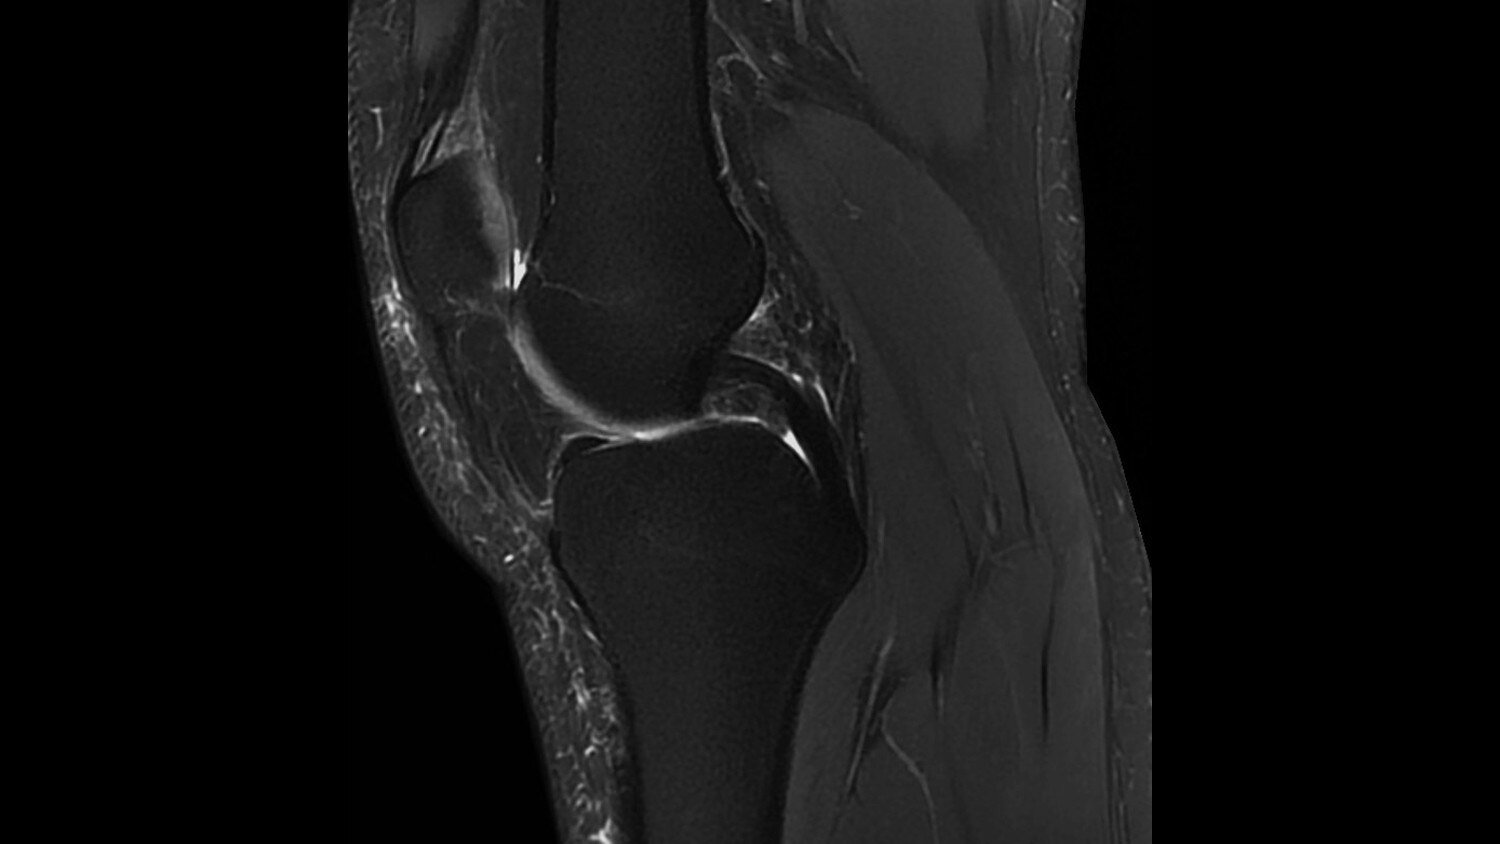

Its full 3.0T magnet and 70 cm bore work together to generate extraordinary image quality without compromises. The result for clinicians is new levels of diagnostic performance.

Intuitive applications help clinicians utilize the full potential of 3.0T MR imaging.